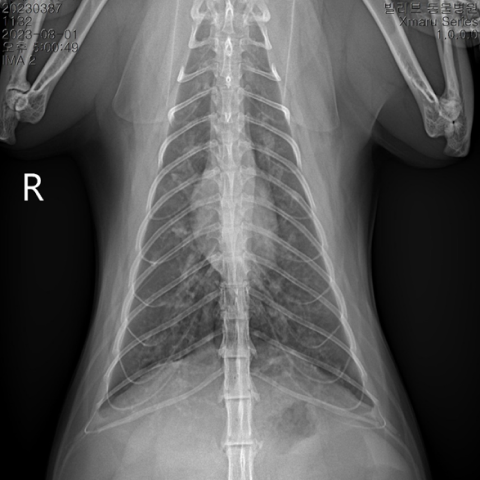

°¡º¿î Áõ»óÀÇ °æ¿ì Áõ»óÀ» ¿ÏÈÇÒ ÀÖ´Â ¾à¹° Ä¡·á¸¦ ¿ì¼±Çϰí, Áõ»óÀÌ Àß ³´Áö ¾Ê°Å³ª ½É°¢ÇÒ °æ¿ì¿¡´Â ¿øÀÎ °¨º°À» À§ÇØ ¹æ»ç¼±, È£Èí±â PCR °Ë»ç, ±â°ü¼¼Ã´ °Ë»ç µîÀ» ÇØº¼ ¼ö ÀÖ½À´Ï´Ù.

±âº»ÀûÀ¸·Î ¿µ»ó °Ë»ç(¹æ»ç¼± °Ë»ç, ÃÊÀ½ÆÄ °Ë»ç)¿Í ¿ä°Ë»ç·Î ¹æ±¤ÀÇ Æó»ö ¿©ºÎ, ¿°Áõ, °á¼®, ¼¼±Õ °¨¿° ¿©ºÎ¸¦ ÆÇ´ÜÇϰí, ³ë·ÉÀ̰ųª Áõ»óÀÌ ½ÉÇÒ °æ¿ì ½ÅÀå ¼öÄ¡¿Í ÀüÇØÁú ¼öÄ¡ µîÀ» üũÇϱâ À§ÇÑ Ç÷¾×°Ë»ç°¡ ÇÊ¿äÇÒ ¼ö ÀÖ½À´Ï´Ù.

°í¾çÀÌÀü¿°¼ºº¹¸·¿°Àº °í¾çÀÌÄڷγª¹ÙÀÌ·¯½º°¡ ¿øÀÎü·Î, °í¾çÀÌ Ã¼³»¿¡ Àẹ »óÅ¿´´ø Äڷγª¹ÙÀÌ·¯½º°¡ ¸Íµ¶¼ºÀ» °¡Áø ¹ÙÀÌ·¯½º·Î º¯À̵Ǿî Àü½Å Àå±â¿¡ ¿°ÁõÀ» ÀÏÀ¸Å°°í, ºóÇ÷, Ȳ´Þ, Èä¼ö, º¹¼ö, ½Å°æ Áõ»óÀ» ÀÏÀ¸Å°´Â Àü¿°¼º ÁúȯÀÔ´Ï´Ù. Àü¿°¼ºº¹¸·¿°Àº ÀÓ»ó Áõ»ó, Ç÷¾× °Ë»ç, Èä/º¹¼ö PCR °Ë»ç, ¹æ»ç¼±, ÃÊÀ½ÆÄ, CT¸¦ ºñ·ÔÇÑ ¿µ»ó °Ë»ç °á°ú¸¦ Á¾ÇÕÀûÀ¸·Î ÆÇ´ÜÇÏ¿© Áø´ÜÇÏ°Ô µË´Ï´Ù. ÀÏ´Ü È®ÁøÀÌ µÇ¸é Ç×¹ÙÀÌ·¯½ºÁ¦¸¦ Åõ¿©ÇÏ´Â °Í¸¸ÀÌ À¯ÀÏÇÑ Ä¡·á ¹æ¹ýÀÔ´Ï´Ù.